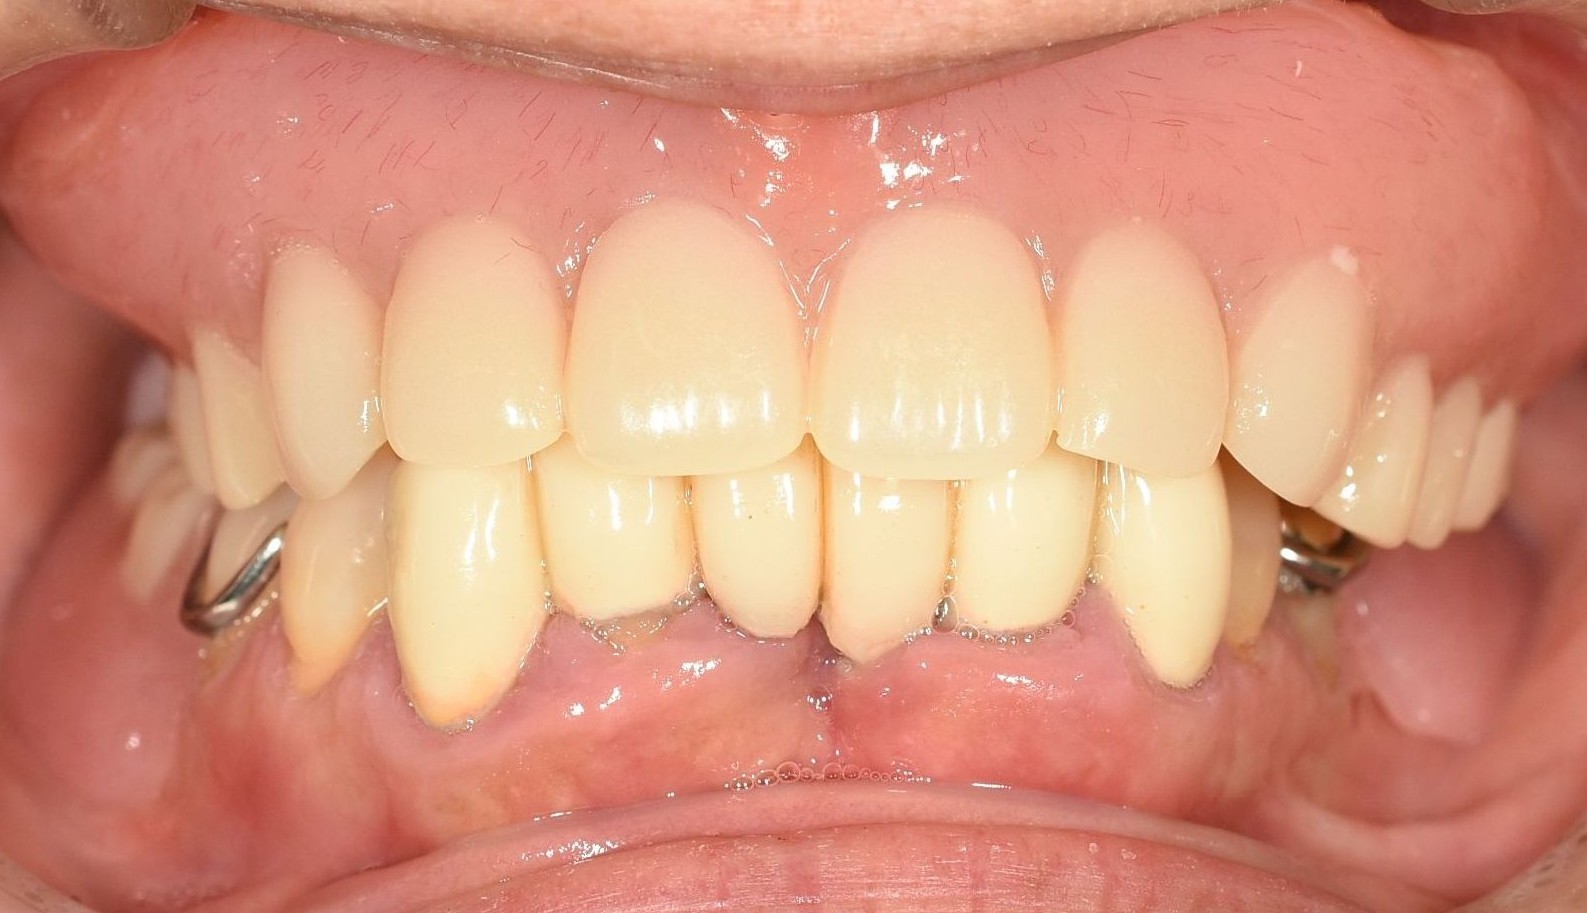

チタン、コバルトクロムを使った「金属床」と呼ばれる入れ歯です。

この素材の一番の長所は、保険適用の入れ歯と比べて「薄い」「壊れにくい」「飲食物の温かみ・冷たさを感じやすい」ことです。特にチタン素材はコバルトクロム素材と比べて重さは2分の1で、金属アレルギーの心配もありません。

価格は約440,000円(税込)。総入れ歯の症例。リスクとしては、金属アレルギーを発症することがあります。

また、保険の入れ歯と比べて圧倒的に薄く作ることができます(約6分の1の薄さ)。お口の中の違和感を軽減できます。